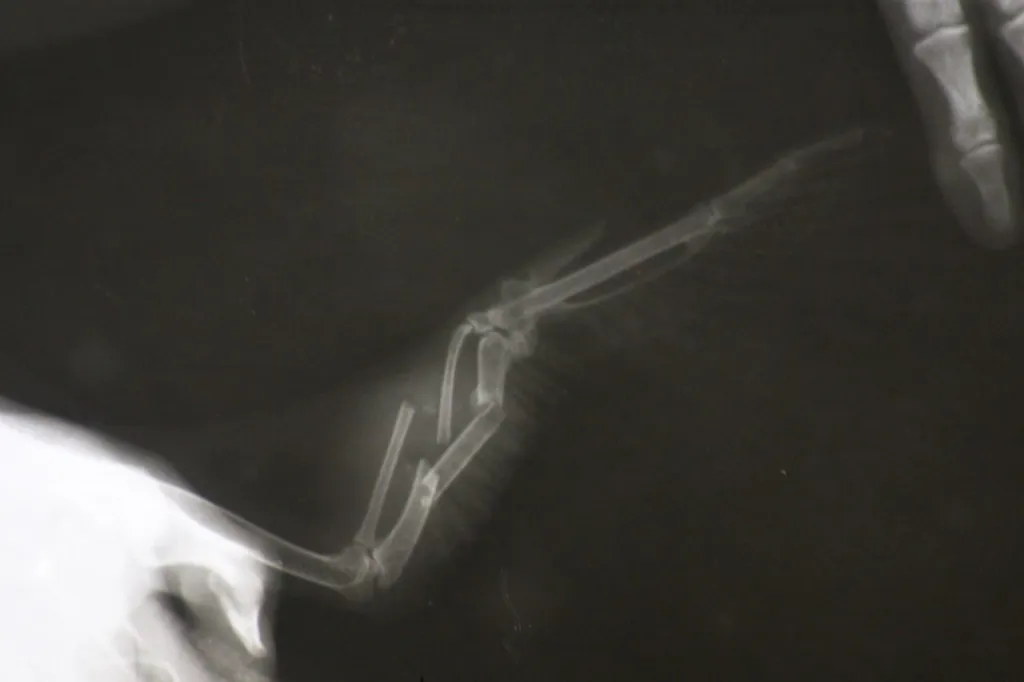

- В Москве выяснилось, что это взрослая выведенная в неволе самка. Как и большинство декоративных водоплавающих и околоводных птиц, в молодом возрасте она подверглась процедуре ампутации кисти - заводчики считают такой метод оправданным, т.к.птица не может улететь с приусадебного участка, и владельцу не нужно следить за своевременной подрезкой перьев в период линьки. "Удобно", не поспоришь, инвалиду деваться некуда. Бонусом помимо перелома имеем трихомоноз, инвазию гельминтами, буйство бактериальной флоры и диарею с примесью крови. - написала Мария Маркина, которая и занимается лечением каролинки.

На сегодняшний день утка прооперирована, состояние стабильное, осталось дождаться сращения перелома, вылечить проблемы с желудочно-кишечным трактом и птица поедет в новый подмосковный дом, обещают кураторы каролинки.